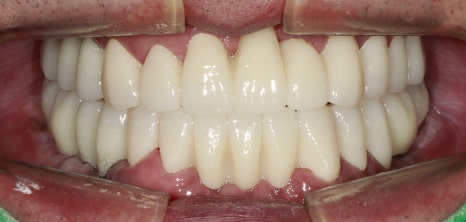

촬영:2023년11월13일

마지막 보철 체결은 환자분께서 수면마취 없이

진행할 수 있을 것 같아 수면 없이 진행하셨습니다.

진료한 치아는 치아 모양과 배열 그리고 색상도

불규칙해 입 주변이 어두워 보였는데

임플란트와 크라운 보철로 치아 모양이 정돈되니

이제 제 나이보다 훨씬 동안으로 보이세요.

얼굴을 봤을 때, 치아가 주는 인상이

크다는 것을 한 번 더 느끼게 해준 진료 케이스였습니다.

최종보철을 제작할 때,

환자분과 심도 있는 이야기를 하기도 하지만

환자의 생김새, 피부 톤이나 연령대를 고려해

치아 모양과 색상을 추천해 드리는 경우가 있어요.

평균적인 보철의 사용 수명은 약 10년~15년으로

여러 가지를 고려해 이번 환자분은 치아색상을 한 톤 밝게 제작해 드렸는데

이 부분이 환자분과 잘 어울려

진료 전 후 차이가 확연하게 달라진 케이스입니다.